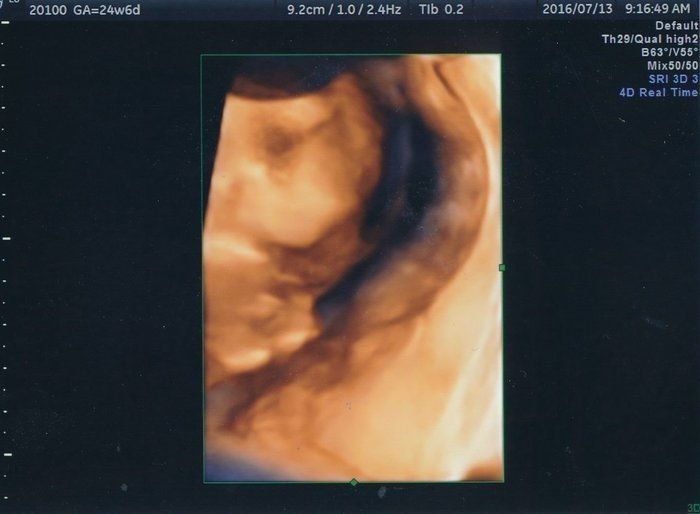

くろみつさんの妊娠24週目のエコー写真 顔の表情がわかり、少しだけ親近感が湧く

お顔のアップの4D画像です。手を顔の前においてこちらを見ていて、少し心配そうなお顔に見えました。おなかの中でぽこぽこしたり、ぐるぐるしたりする感覚がありましたが、いまいち胎動なのかはわからず、「あ、動いた」と感じるような胎動に感動することがないまま日々が過ぎました。アイスクリームとチョコレートが大好きになり、我慢するのがつらかったです。